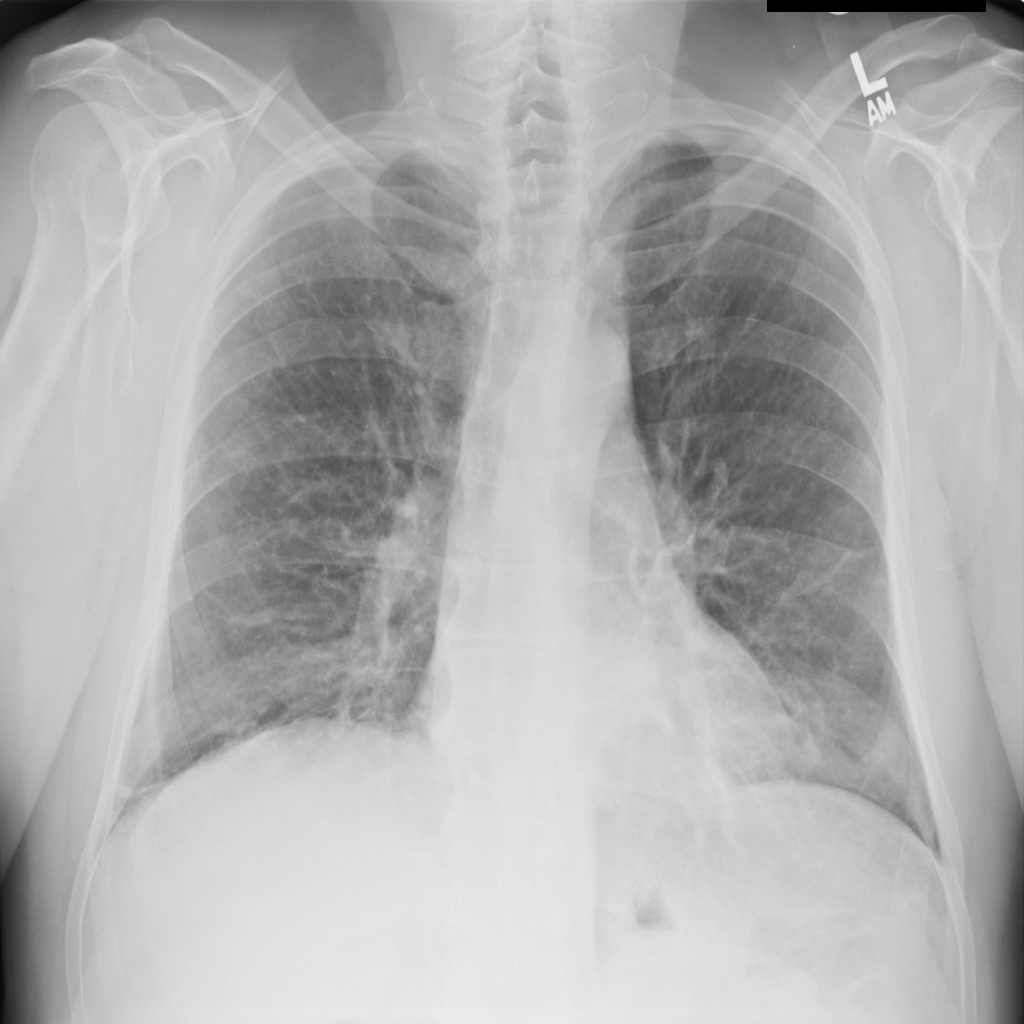

PAT-E960 · IMG-002Fibrosis

PAT-E960 · IMG-002

PA